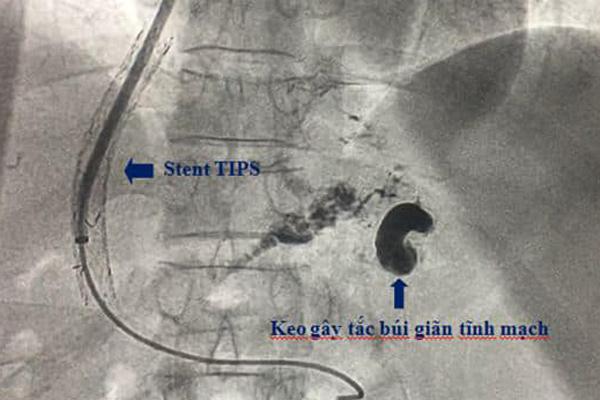

Bác sĩ dùng phương pháp TIPS can thiệp đặt stent cho bệnh nhân

Hội chẩn khẩn cấp, các bác sĩ quyết định làm thủ thuật can thiệp tạo luồng thông cửa - chủ trong gan qua đường tĩnh mạch cảnh (TIPS). Sau hơn 1 giờ, ekip can thiệp của khoa Chẩn đoán hình ảnh đã cầm máu thành công và đặt stent cho bệh nhân.